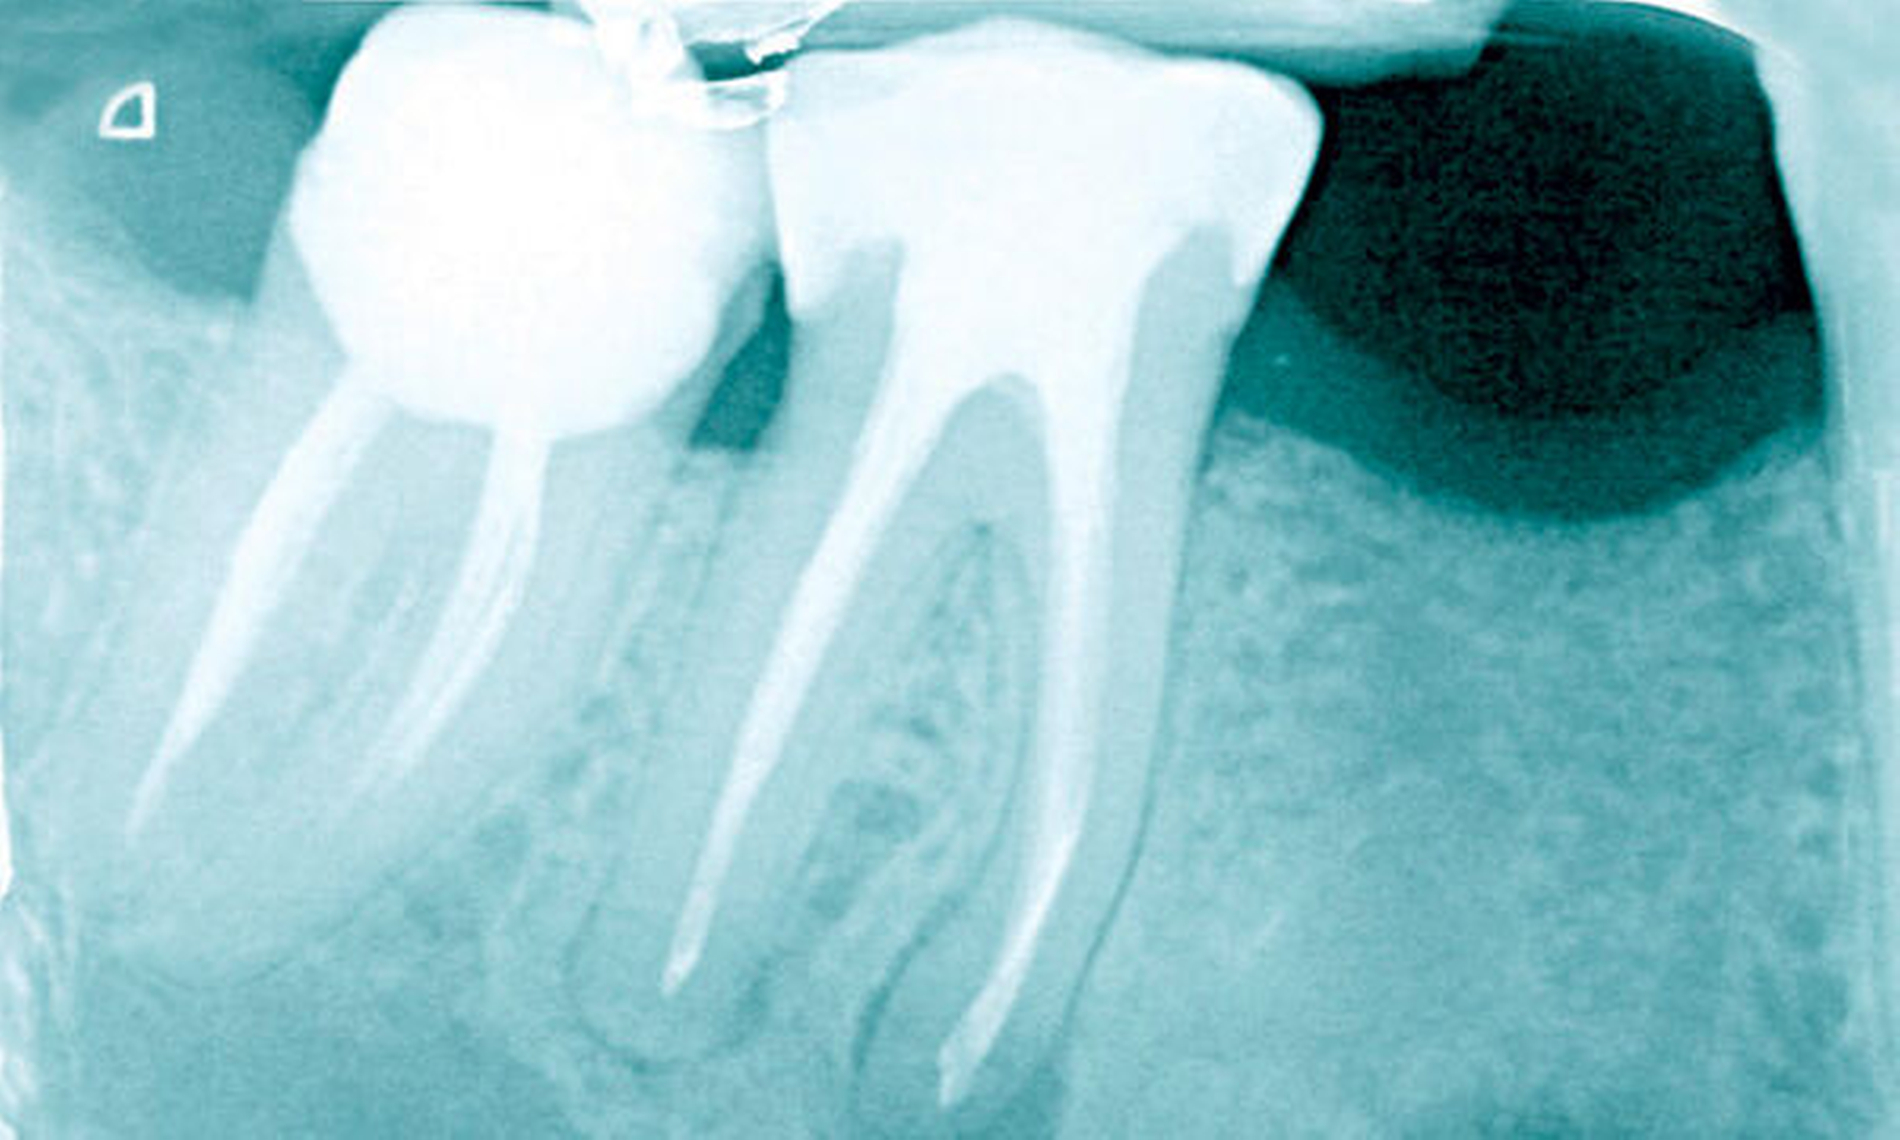

Was spielt sich im Zahninnern und im periapikalen Gewebe ab, wenn Entzündungen entstehen? Warum sind Behandlungen erfolgreich oder scheitern? Antworten darauf könnte die Mikrobiomforschung geben, die mit neuen Untersuchungsmethoden das Keimspektrum des Endodonts in den Fokus genommen hat. Prof. Dr. Ali Al-Ahmad und Prof. Dr. Elmar Hellwig, Freiburg, skizzieren den aktuellen Wissensstand.